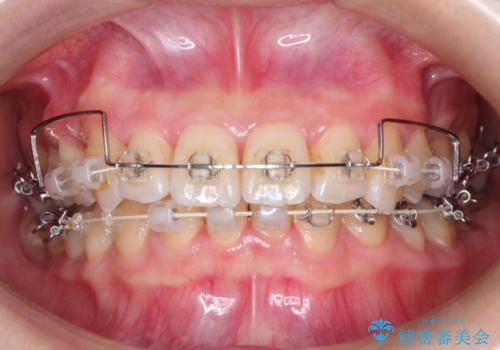

抜歯ありワイヤー矯正にて治療を行い、抜歯する歯に関しては虫歯で抜歯が必要な部分を有効活用することで、健康な歯を保存するように努めました。

噛み合わせが深い過蓋咬合という状態でもあったため、下の歯の装置をつけたり、嚙み合わせを上げる(下の歯が見える状態にする)ことにたいへんに苦労した症例でした。